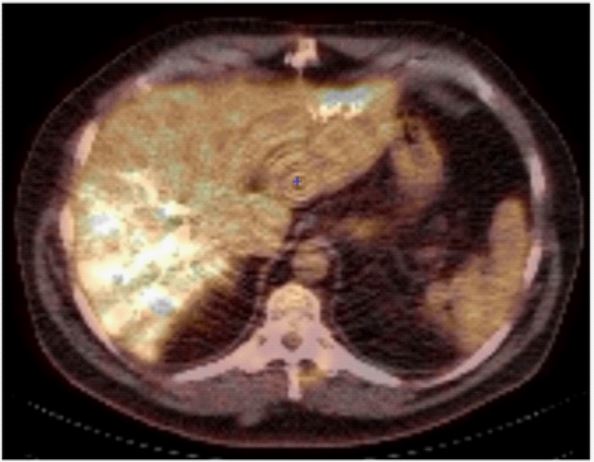

A 53-year-old male patient was diagnosed with an occlusive sigmoid colic cancer with synchronous multiple bilobar liver metastasis. Firstly, an anterior rectal resection was performed combined to a complete tumour clearance of the left hemiliver, by resection of five metastasis. He received systemic chemotherapy, and right portal embolization before second step right hepatectomy. PET-CT performed five months after the first step resection and prior to the second stage hepatectomy showed abnormal metabolic activity in segments V and VI, as long as in the resection site of segment II (SUV 4,8) (Figure 2). During the right hepatectomy, the former section site of segment II was removed, and histopathology showed features of fibrous scar tissue with no evidence of malignancy.

Figure 2: Representative images of PET-CT metabolic activity in the site of previous wedge resection on segment II (SUV 4,8)